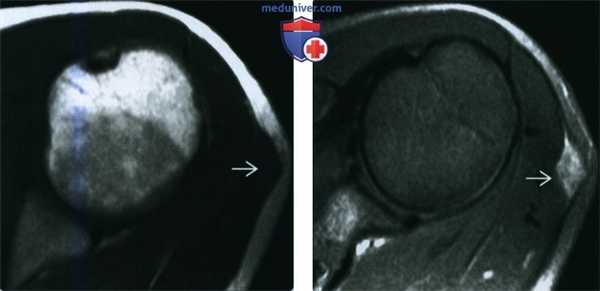

(Слева) МРТ Т1 ВИ, аксиальный срез: определяется изоинтенсивное по отношению к мышцам образование, смещающее подкожную жировую клетчатку, которое не может быть полностью отделено от дельтовидной мышцы.

(Справа) МРТ, постконтрастные Т1 ВИ, режим подавления сигнала от жира, аксиальный срез: у этого же пациента определяется гетерогенное контрастирование образования. Доброкачественные фиброзные образования имеют тенденцию к гипоинтенсивному сигналу на Т1- и Т2ВИ (на этой томограмме не определяется). Другой характерной чертой является слабое контрастирование.